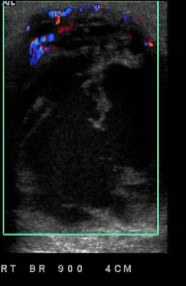

Identify this image.

Breast abscess